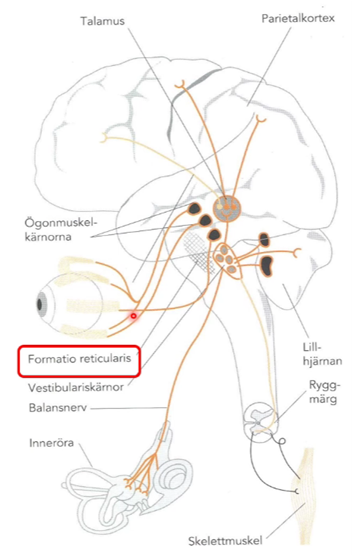

- Formatio reticularis tar emot impulser från synen, ögonmuskler, balansnerven i innerörat, liksom perifera receptorer i muskler och senor. Vartefter det bearbetas på högre nivå i storhjärnan

Beskriv översiktligt hur balanssystemet fungerar

- Syn, vestibulär info, proprioception och hudens känsel integreras i hjärnstammens vestibulariskärnor och har också hjälp av cerebellum, medvetandet kan påverka genom att vi vill stå stadigare eller slappna av mer

- Styrsignaler skickas sedan ut till muskler (ögonmuskler, nacken, ryggen, vadmuskler osv) och vi kan motta ny information från synen osv vilket ger nya kommandon

Vad orsakas yrsel av?

- Störningar i receptororganen

- Störningar i CNS

- Kombinationer